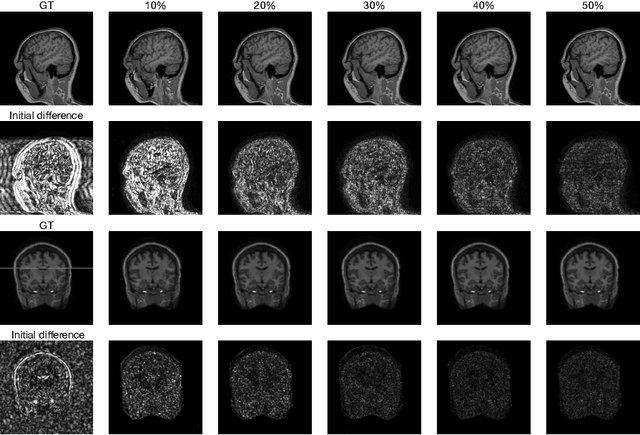

Abstract:Fast Magnetic Resonance Imaging (MRI) is highly in demand for many clinical applications in order to reduce the scanning cost and improve the patient experience. This can also potentially increase the image quality by reducing the motion artefacts and contrast washout. However, once an image field of view and the desired resolution are chosen, the minimum scanning time is normally determined by the requirement of acquiring sufficient raw data to meet the Nyquist-Shannon sampling criteria. Compressive Sensing (CS) theory has been perfectly matched to the MRI scanning sequence design with much less required raw data for the image reconstruction. Inspired by recent advances in deep learning for solving various inverse problems, we propose a conditional Generative Adversarial Networks-based deep learning framework for de-aliasing and reconstructing MRI images from highly undersampled data with great promise to accelerate the data acquisition process. By coupling an innovative content loss with the adversarial loss our de-aliasing results are more realistic. Furthermore, we propose a refinement learning procedure for training the generator network, which can stabilise the training with fast convergence and less parameter tuning. We demonstrate that the proposed framework outperforms state-of-the-art CS-MRI methods, in terms of reconstruction error and perceptual image quality. In addition, our method can reconstruct each image in 0.22ms--0.37ms, which is promising for real-time applications.